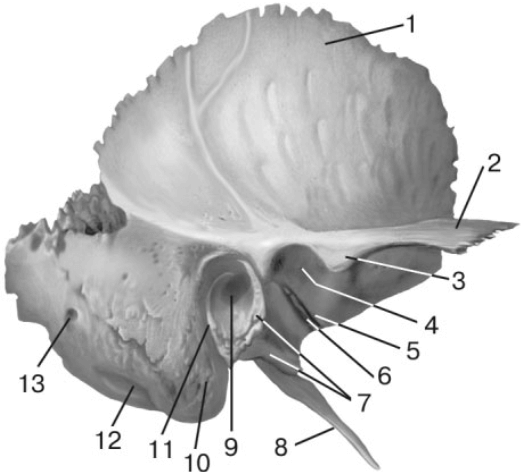

Анатомия и особенности фиссуры петротимпаника